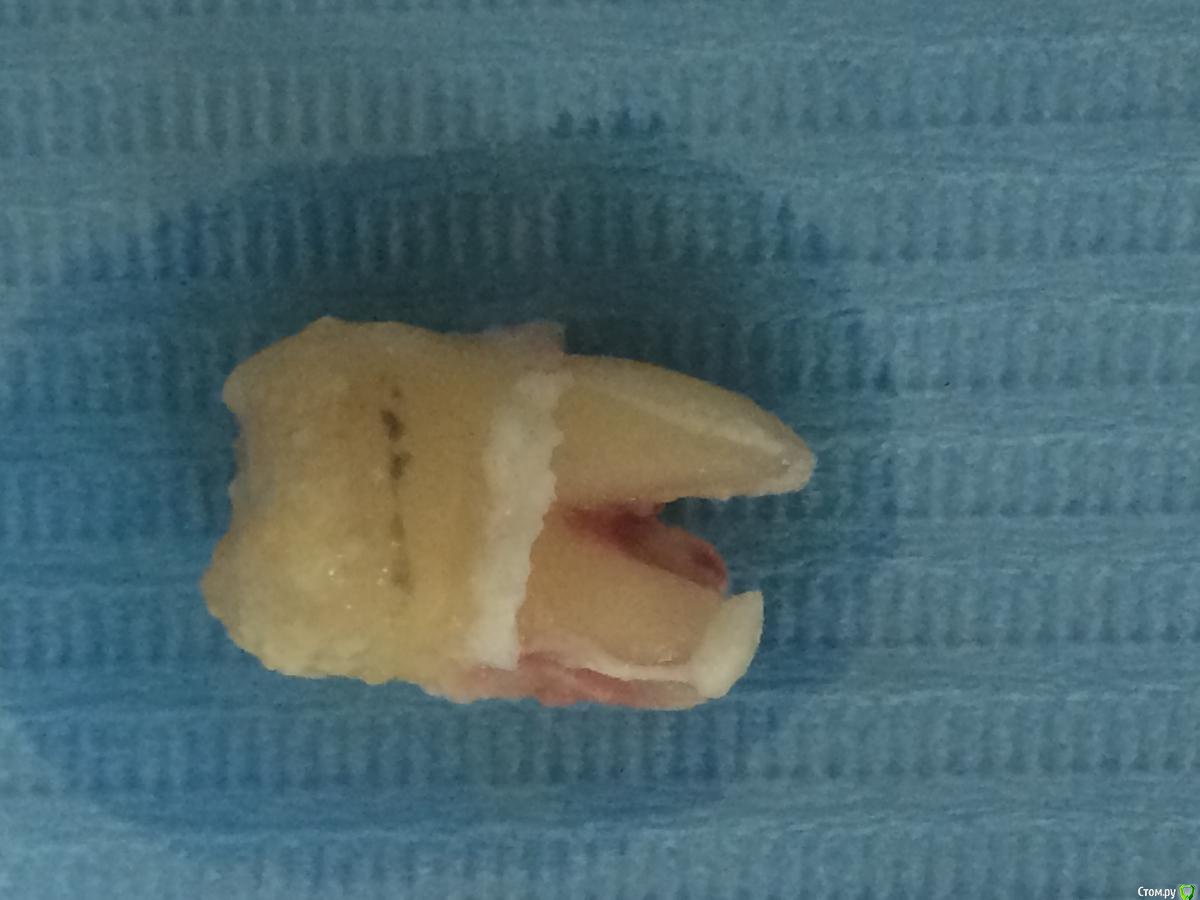

Фарид Расулыч Опубликовано 22 декабря, 2014 Поделиться Опубликовано 22 декабря, 2014 Свежий урожай) только с "грядки" 10 Ссылка на комментарий